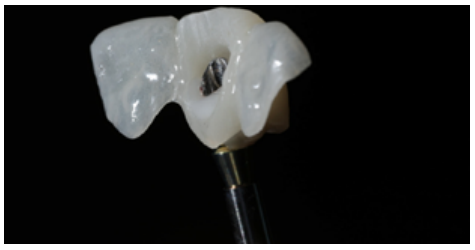

Before starting the provisional screw-retained restoration on the OII, the correct position of the abutment in terms of the provisional prosthesis was verified. The abutment was relined with the provisional through the use of flowable composite (Figures 8 and 9).

Preparation of the emergence profile

To perform the emergence profile (EP), the ideal position of the gingival margin was determined, which had to coincide with the position of the cervical line (amelocemental junction) of the ULCI (Figures 10-13B).